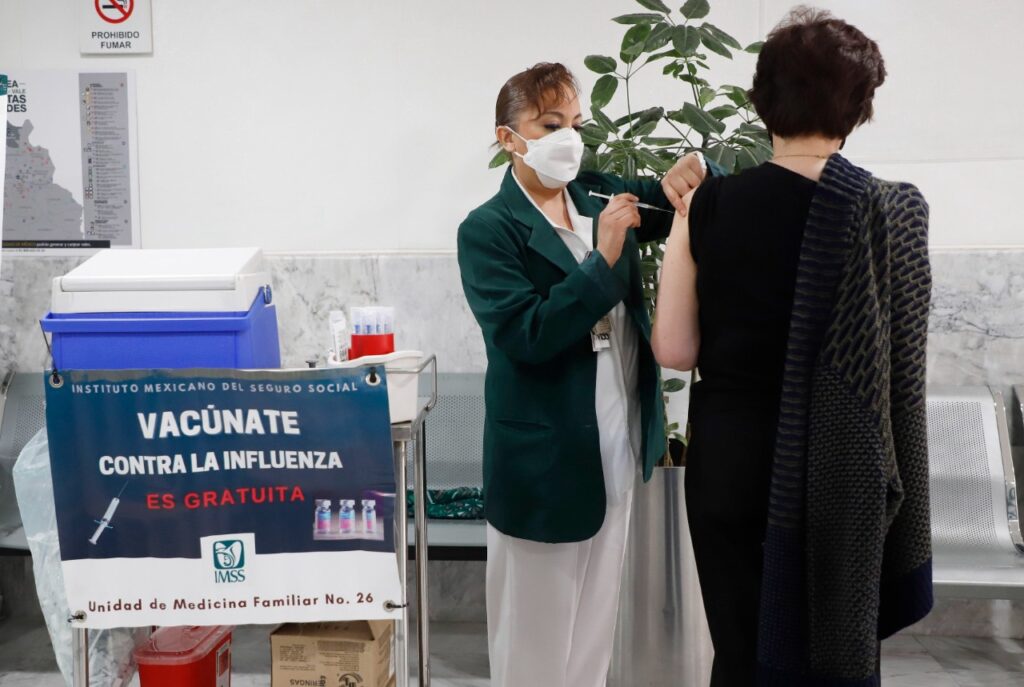

Oaxaca intensifica vacunación contra sarampión, COVID-19 e influenza ante riesgos epidemiológicos

Oaxaca de Juárez, Oaxsca, a 2 de marzo de 2026. – Autoridades de los Servicios de Salud de Oaxaca (SSO) informaron que se reforzó la campaña de vacunación contra sarampión, COVID-19 e influenza en distintas regiones del estado, con el objetivo de prevenir brotes, reducir hospitalizaciones y proteger a grupos vulnerables. La estrategia incluye módulos […]

IMSS Oaxaca exhorta a reforzar medidas preventivas y aplicarse la vacuna contra la influenza ante el descenso de temperatura

Ante el descenso de la temperatura y los cambios bruscos de clima registrados en la entidad, el Instituto Mexicano del Seguro Social (IMSS) en Oaxaca hizo un llamado a la población para extremar precauciones, reforzar las medidas de prevención y acudir a vacunarse contra la influenza, a fin de evitar enfermedades respiratorias y proteger la […]

Oaxaca arranca campaña de vacunación invernal: más de un millón de dosis contra influenza, Covid-19 y neumococo

Oaxaca de Juárez, Oaxaca, a 14 de octubre de 2025.– Los Servicios de Salud de Oaxaca (SSO) pusieron en marcha ayer, la Campaña de Vacunación para la Temporada Invernal 2025–2026, con el objetivo de aplicar un millón 129 mil 425 dosis de vacunas contra la influenza estacional, la Covid-19 y el neumococo, a fin de […]